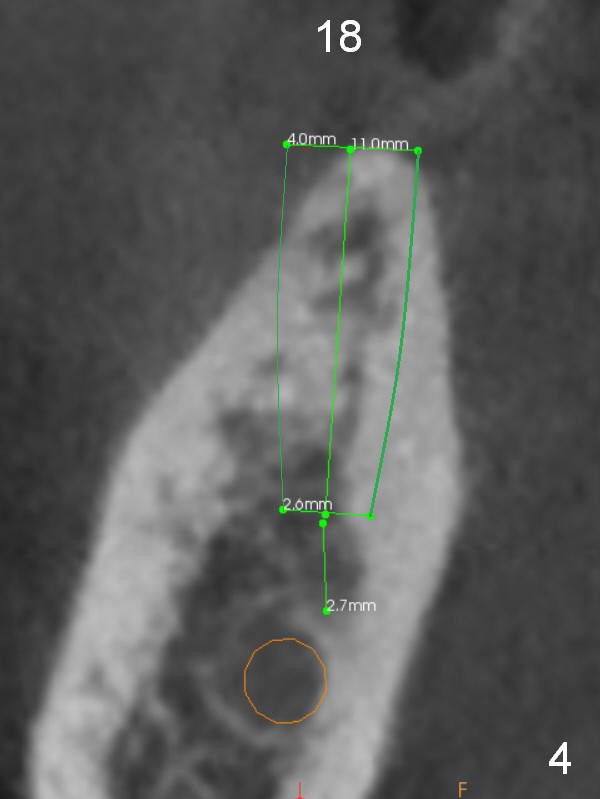

A 71-year-old man requests restoration at #18-20 (Fig.1). Placing implants at the narrow ridge of the sites of #18 and 19 is quite challenging (Fig.3,4), as compared that at #31 (Fig.5). Since the bone density at the crest is high (1200-1500 u), use a surgical high speed fissure bur for sectioning the crest, followed by BEB at 11 mm. It appears safer to place 1-piece implant (Fig.3) than 2-piece one (Fig.4). Since the total mesiodistal distance for #18-20 is 18 mm, splinting the three-units should be a sound treatment option.